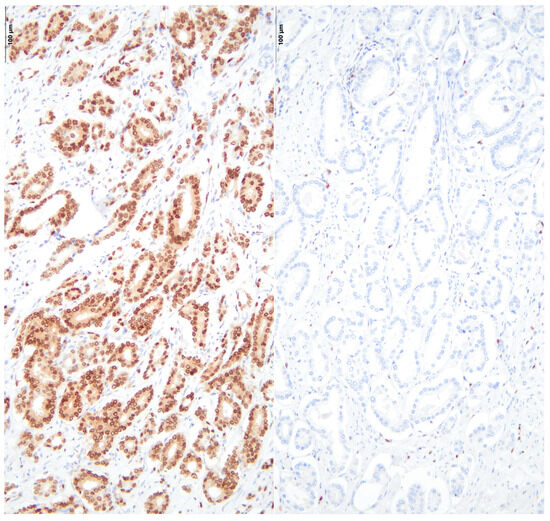

2.7. Immunohistochemical Stainings